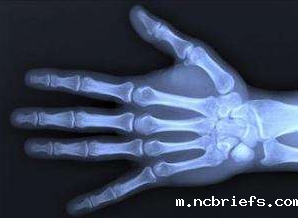

最常见的测骨龄的办法就是直接去医院放射科拍片,然后根据拍片的结果来判断自己的骨龄情况,最后得出骨骼的年龄,这种办法不仅价格是大多数人的承受范围而且相比较也方便,基本各个医院都能够提供。

超声骨密度检测仪厂家山东国康研发的检测人体骨骼密度的仪器既可以检测骨密度,也可以帮助检测人体骨龄,并且针对儿童可以帮助预测到未来的身高发展情况。对于自己的骨骼年龄想了解的更多更具体一点,可以选择去专业的超声骨密度检测仪检测,进行一系列的检测后就可以得出结果,这样的检测结果也是更准确,更可信的。